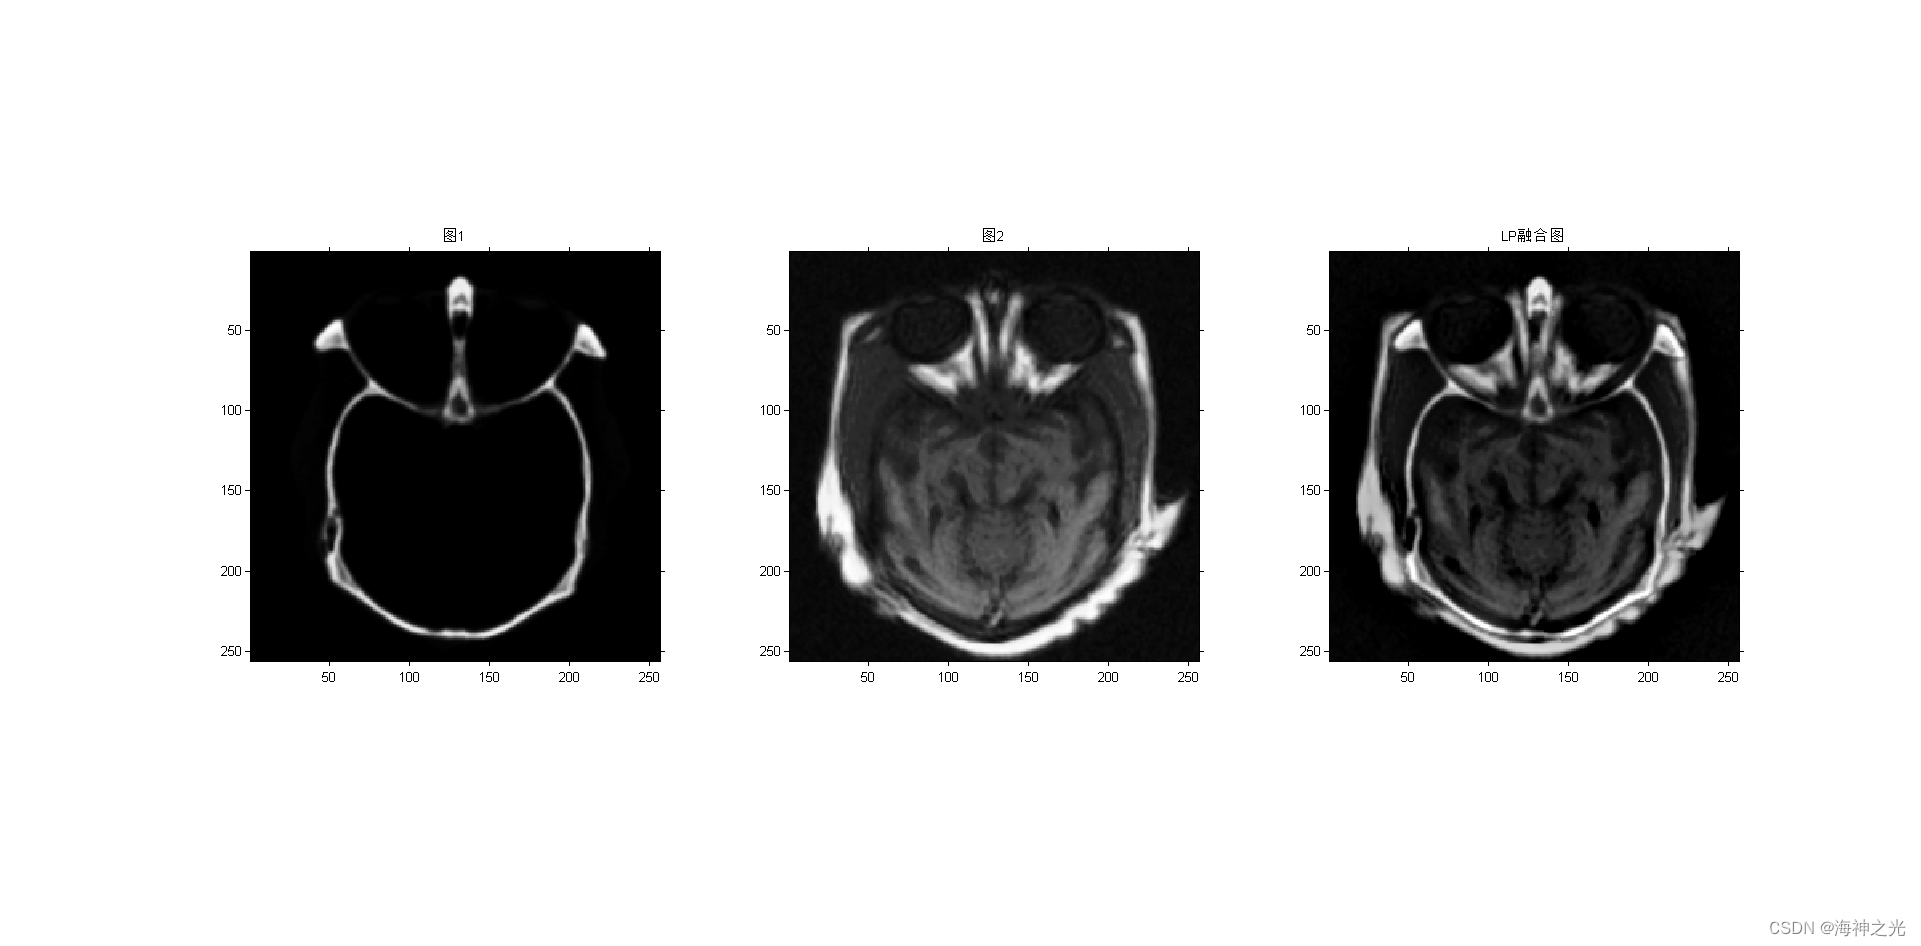

figure;subplot(131);imshow(image_input1);title(‘图1’)

subplot(132);imshow(image_input2);title(‘图2’)

subplot(133);

F = lp_fuse(A, B, level, 3, 3); %LP

title(‘LP融合图’)